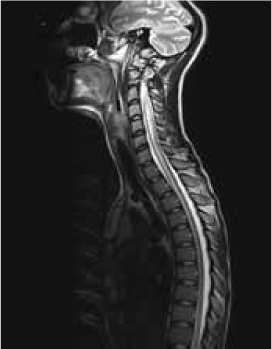

Magnetic resonance imaging (MRI) of the brain showed symmetrically increased T2-weighted and fluid-attenuated inversion recovery signal in the central pons (Figure 1) and in the striatum of the basal ganglia (Figure 2), with no contrast enhancement seen on corresponding T1-weighted postgadolinium images (Figures 3 and 4). Spinal MRI (Figure 5) demonstrated high signal on T2-weighted images from the area postrema in the medulla extending caudally to the T9 thoracic segment, with marked cord swelling and mild enhancement on T1-weighted postcontrast studies (Figure 6), in keeping with a longitudinally extensive inflammatory myelitis.

Magnetic resonance image of spine shows longitudinally extensive intrinsic increased cord signal on sagittal T2-weighted sequences

Magnetic resonance imaging shows longitudinally extensive cord signal abnormality with peripheral enhancement on sagittal T1-weighted postcontrast sequence